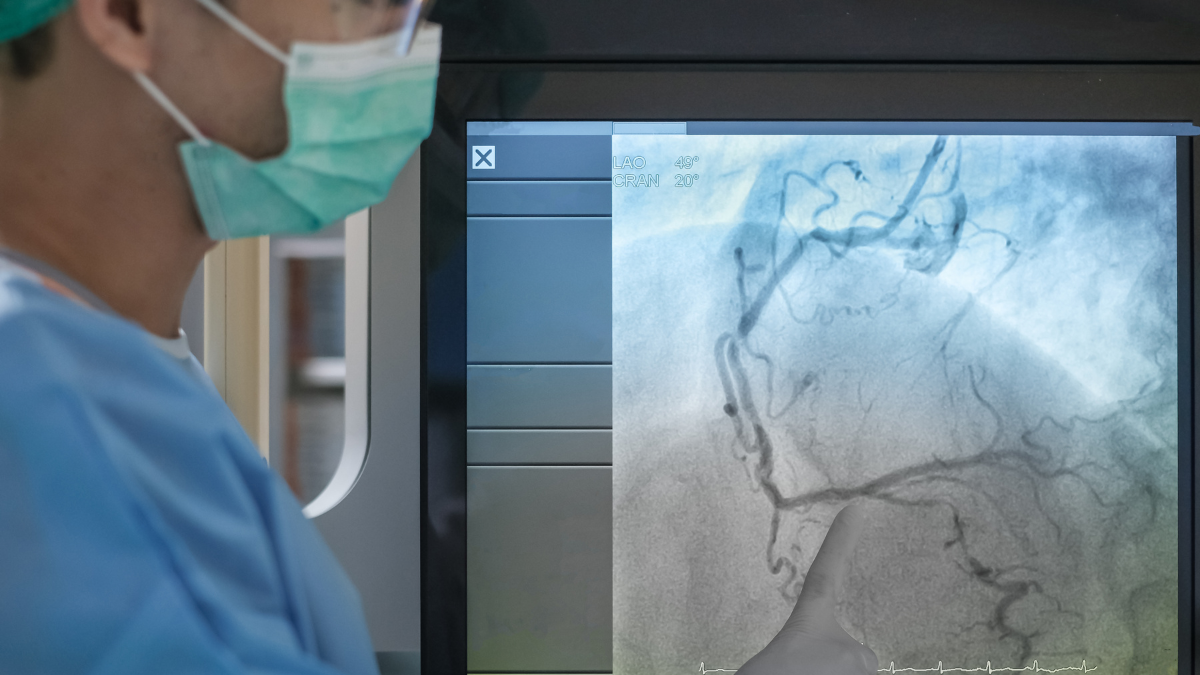

The Key to Heart Health: Understanding Coronary Angiography

Coronary angiography is a minimally invasive procedure to diagnose and prevent heart conditions like…